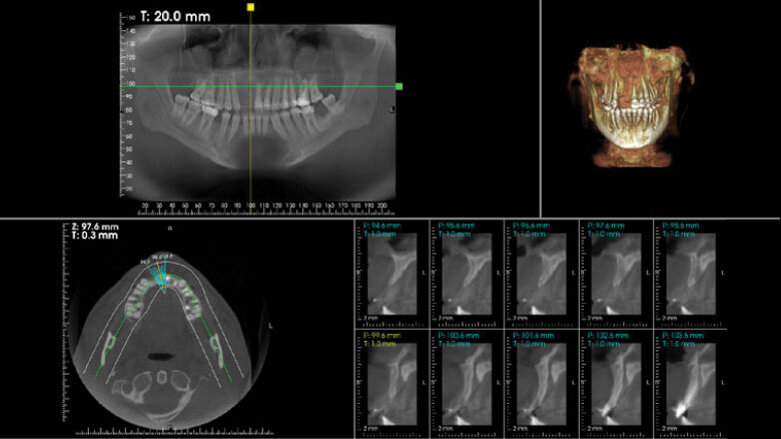

Figure 11: CBCT cross-sectional view of sites no 7 and 8 revealed inadequate ridge width to support implant with restoration.

Figure 12: Preoperative view showing the amount of horizontal bone deficiency in the area.

A 33 years-old male patient was visiting our clinic to replace missing teeth no 7 and 8. He was medically fit and mentioned that his teeth were lost due to car accident few years back. Intraoral examination shows absence of space for implant placement and restoration, orthodontic treatment was conducted for 18 sessions followed by surgical implant placement after stabilization of the occlusion. Following the restoration of the space, the amount of horizontal bone loss was evident both clinically and on CAT examinations (Fig.10, 11). A linear incision with mucoperiosteal flap elevation were conducted, the amount of horizontal bone loss was advanced (Fig. 12), which was an indication for autologous bone graft, patient refused to undergo an invasive surgery so PRF associated bovine bone was planned in the area. Blood withdrawal and centrifugation were done with preparation of both L-PRF membranes and sticky bone (bovine bone associated PRF) (Fig.13, 14,15). The combination was placed on the host bone deficiency and covered by a first layer of L-PRF membranes in order to stabilize the graft and insure hemostasis, the second layer of L-PRF membranes covered the cross linked collagen membrane placed in the same area and covering the first entity (Fig.16).